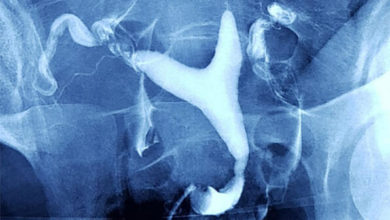

Rahim filmi (HSG) nedir?

Histerosalpingografi (HSG) veya Türkçe deyişle rahim filmi jinekolojide rahim içinin ve kanalların yapısal ve işlevsel özelliklerini incelemede kullanılan bir yöntemdir. İnfertilite (kısırlık) değerlendirmesinde istenen…

Histerosalpingografi (hsg)

Bu muayene çoğu zaman, rahmin (uterus) ve fallop tüplerinin daha yakından incelenmesi amacıyla yapılır. Histerosalpingografi, rahmin (histero) ve fallop tüplerinin…

İlaçlı rahim filmi (histerosalphingografi) nedir?

Rahim ağzından bir alet yardımıyla rahim içine ilaç verilip tüplerin ve rahim içinin araştırıldığı bir yöntemdir. Histerosalphingografide özel bir sıvı…